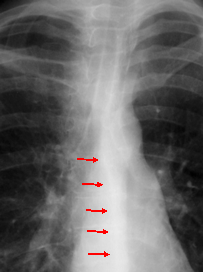

Azygo-esophageal recess